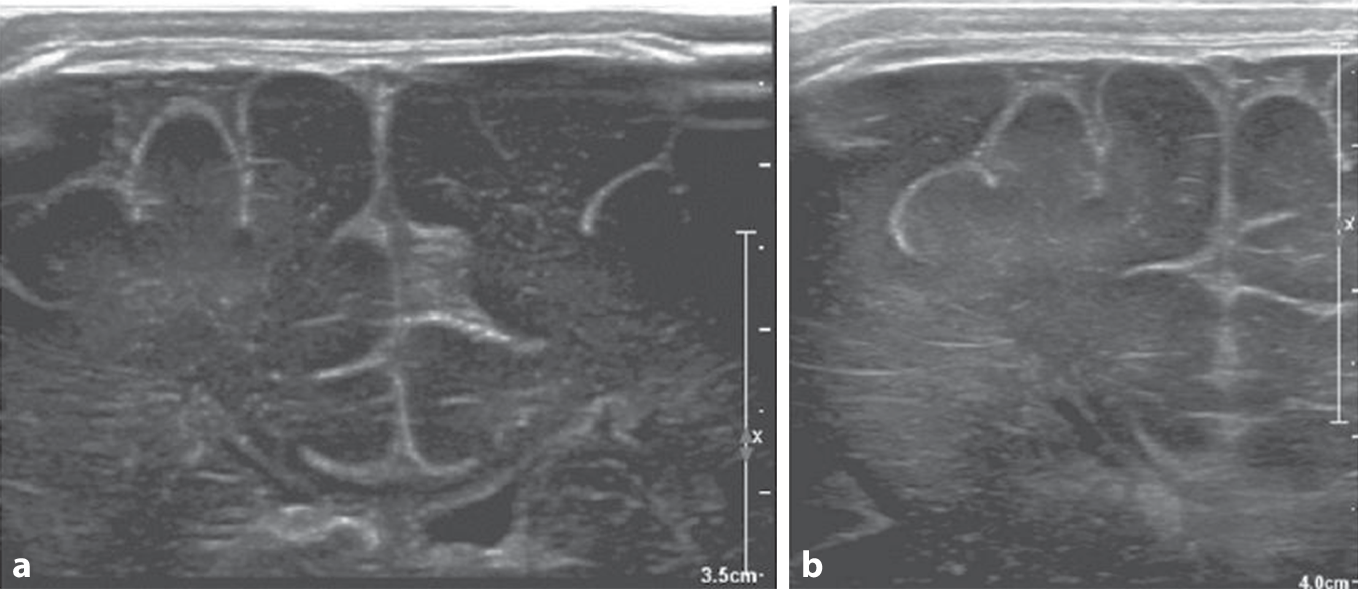

Am Vortag fiel erstmals auf, dass das sechs Tage alte Neugeborene wiederholt für einige Sekunden mit dem linken Arm zuckte. Am folgenden Tag drehte es im wachen Zustand mehrmals für etwa zwei Minuten den Kopf und die Augen nach links. Laut Eltern waren Schwangerschaft und Geburt unauffällig. Abb. 1, 2 und 3 zeigen die Hirnsonographie, die kranielle Magnetresonanztomographie (MRT, am neunten Lebenstag) und das Elektroenzephalogramm (EEG).

Abb. 1

Sonographie des zentralen Nervensystems, koronar. a Schallkopf mittig eingestellt, b Fokus auf die rechte Hemisphäre des Kindes